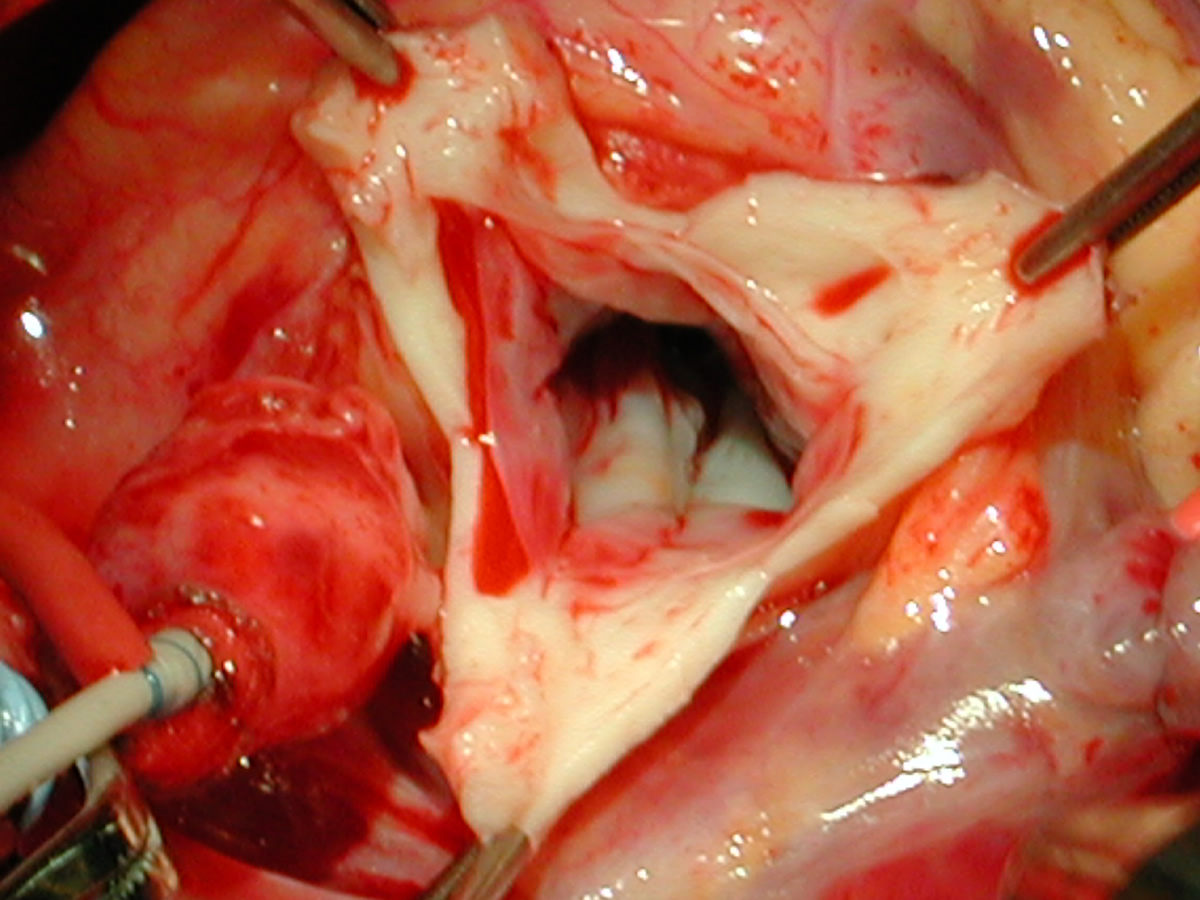

Figures 28 & 29: Completed noncoronary cusp patch. Figure 30: A portion of thick intimal hyperplasia adjacent to the left coronary orifice is sharply resected with a no. 11 blade. Figure 31: Completed resection showing no residual intimal thickness.

Figure Figure Figure Figure